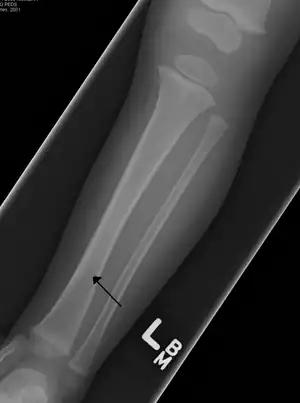

| A toddler's fracture | |

The cause is often a twisting motion over a planted foot.[1] This may occur as the result tripping or other minor events.[1] It generally occurs in the distal thirds of the tibia, is undisplaced, and has a spiral pattern.[1] Diagnosis is often based on symptoms and examination, with initial X-rays appearing normal in about half of cases.[1]

The initial radiographical images may be inconspicuous (a faint oblique line) and often even completely normal.[6] After 1–2 weeks however, callus formation develops.